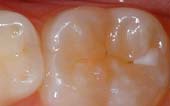

Your pediatric dentist may also recommend protective sealants or home fluoride treatments for your child. Sealants can be applied to your child's molars to prevent decay on hard to clean surfaces.

AA sealant is a protective coating that is applied to the chewing surfaces (grooves) of the back teeth (premolars and molars), where four out of five cavities in children are found. This sealant acts as a barrier to food, plaque and acid, thus protecting the decay-prone areas of the teeth.